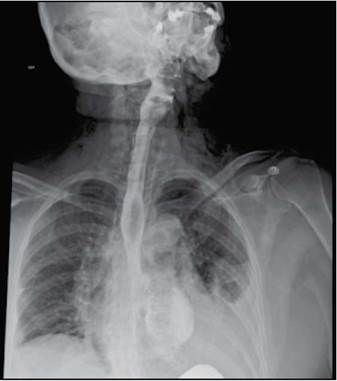

Mujer de 58 años, ingresa a urgencias por presentar dolor pleurítico en hemitórax izquierdo de fuerte intensidad, irradiada a dorso, asociado a tos seca y disnea progresiva. No tiene antecedentes de importancia. Al ingreso con tensión arterial: 80/46 mmHg, frecuencia cardiaca 112 por minuto, frecuencia respiratoria: 22 por minuto y temperatura: 39°C. Al examen físico: disminución del murmullo vesicular basal izquierdo con estertores y llenado capilar prolongado. Se toman laboratorios que muestran leucocitosis, neutrofilia y elevación de azoados. Se solicita radiografía de tórax que muestra consolidación basal izquierda y enfisema subcutáneo en cuello. Es trasladada a unidad de cuidados intensivos con choque séptico de origen pulmonar. Al reinterrogar a la paciente refiere episodio de atoramiento alimentario previo al inicio del cuadro, acompañado de múltiples episodios eméticos. Se sospecha síndrome de Boerhaave (perforación esofágica espontánea) y mediastinitis aguda, obteniéndose esofagograma que evidencia hallazgos compatibles con perforación esofágica distal (Figura 1) y tomografía de tórax que muestra neumomediastino y derrame pleural con consolidación basal izquierda (Figura 2), por lo cual se instaura vancomicina y piperacilina tazobactam. Es llevada a cirugía donde encuentran perforación de esófago torácico (Figura 3), con mediastinitis, pericarditis y pleuritis izquierda. No fue posible cirugía definitiva ante la inestabilidad de la paciente, únicamente se realizan drenaje de material purulento mediastinal, pleural, pericárdico y colocación de tubo en mediastino y tórax. A las 24 horas se realiza esofaguectomía media y distal con esofagostomía proximal cervical. Evoluciona tórpidamente, se documenta bacteriemia por Serratia marcescens resistente, se indica meropenem. Luego de múltiples lavados mediastinales, ventilación mecánica prolongada y 45 días en unidad de cuidados intensivos, progresa a falla orgánica múltiple y fallece.